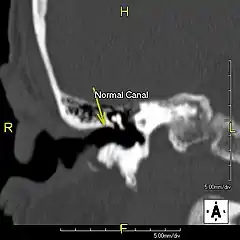

L'exostose du surfeur ou oreille de surfeur est une exostose, c'est-à-dire une croissance osseuse anormale, qui pousse vers l'intérieur du conduit auditif[1]. L'os entourant le conduit auditif réagit à l'agression thermique et mécanique de l'eau froide et de ses turbulences, par une nouvelle croissance osseuse qui a pour effet de resserrer le conduit auditif.

Du fait de la réduction du diamètre du conduit auditif, l'eau et le cérumen peuvent rester piégés entre la masse osseuse et le tympan et provoquer ainsi une infection comme une otite externe, particulièrement douloureuse.

Le traitement de l'exostose est chirurgical, de préférence avant une obstruction avancée. L’intervention, délicate et pouvant laisser des séquelles (perte d'audition, acouphènes…)[4] s'effectue sous anesthésie générale. L'abrasion de l'os s'effectue soit par le conduit auditif soit en faisant une incision derrière le pavillon de l'oreille. La préservation de la peau interne du conduit est déterminante pour la restauration d'une couverture cutanée optimale après l'opération.